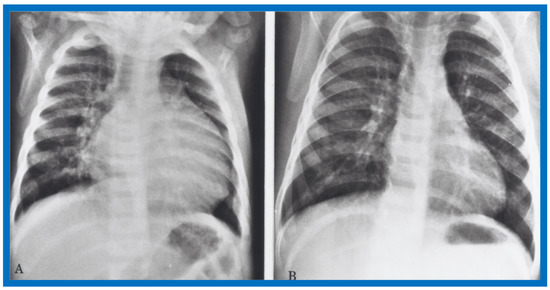

Examples of improvement in LV dimension on echo studies are shown in Figure 40 and Figure 41. The cardiac size and pulmonary venous congestion on chest roentgenograms improved in the hydralazine group (Figure 42 and Figure 43). No significant changes in any of these parameters occurred in the control group.

Figure 42.

Antero-posterior view of chest x-rays prior to (A) and following (B) hydralazine therapy. Moderate cardiomegaly and pulmonary venous congestion were seen prior to therapy (A) which improved remarkably after therapy (B).

Figure 43.

Antero-posterior view of chest x-rays prior to (A) and following (B) hydralazine therapy from a different infant. Moderate cardiomegaly with pulmonary venous congestion was seen prior to therapy (A) which improved remarkably after therapy (B), similar to that seen in Figure 42.